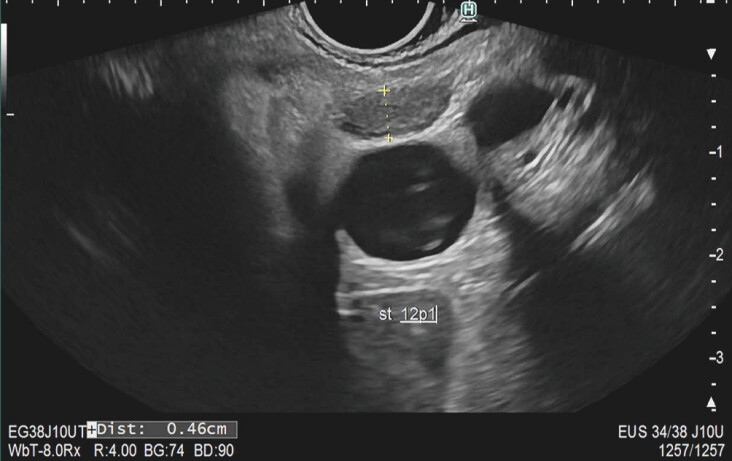

Methods: A cross-sectional survey study was conducted among 24 endosonographers. Participants reviewed 42 EUS images from iCCA and pCCA patients, classifying LNs based on six characteristics (demarcation, shape, echogenicity, homogeneity, suspiciousness, and need to retrieve tissue). Interobserver agreement was determined using Light's kappa statistics. Accuracy, sensitivity, and specificity in identifying malignant LNs were calculated.

Results: Overall kappa values indicated moderate to fair agreement on LN characteristics, with Kappa values of 0.24 for demarcation, 0.45 for shape, 0.38 for echogenicity, 0.52 for homogeneity, and 0.36 for suspiciousness. Overall accuracy of endosonographers in correctly identifying malignant LNs was 62%, with individual accuracy ranging from 44 to 75%. Sensitivity was 60% (range: 29%-90%) and specificity was 64% (range: 28%-89%).